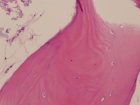

20 year old male with worsening left hip pain, the patient has pain with transfers and has minimal ambulation

Zoom image: Cell stain Cell stain.